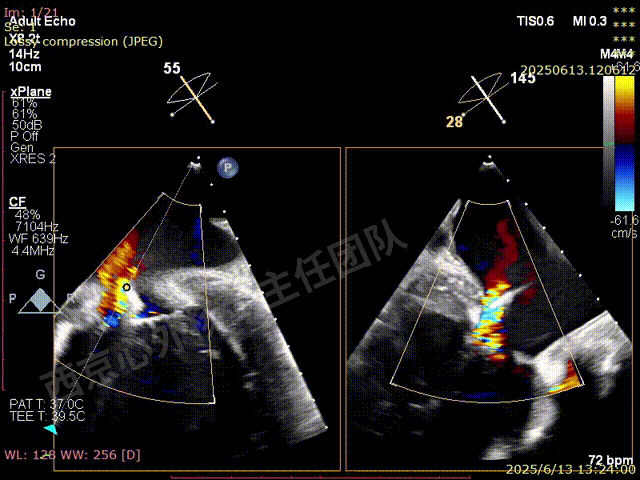

夹子关闭后检查夹子两侧反流

第一枚XTW释放后评估,外侧反流基本消失,内侧仍然有中度以上反流

第二枚XT于第一枚夹子内侧瓣上调整

第二枚XT关闭后评估,trace

二尖瓣平均跨瓣压差1mmHg

释放后评估,反流降至1+,组织桥稳定